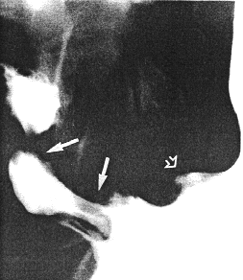

Case 29.2 I.H., 59 year old male, presented with longstanding epigastric pain and malaena. Radiographic examination showed a large ulcer in the posterior wall of the midcorpus. Endoscopic biopsy confirmed the ulcer; the gastric mucosa showed intestinal metaplasia with prominent acute and chronic inflammatory cells, diagnosed as subacute gastritis. No evidence of malignancy was found. After anti-ulcer therapy the patient was temporarily lost to follow-up, but reappeared three years later. Radiographic examination showed the following: after the first two mouthfuls of barium a large ulcer on the posterior wall of the corpus was evident as before (Fig. 29.2A). Before barium entered the duodenum a constant, deep spastic incisura was seen in the pyloric region of the distal greater curvature; swallowing more barium showed it to be due to contraction of the left pyloric loop (Fig. 29.2B). The pyloric sphincteric cylinder between the left loop and the pyloric aperture remained partially contracted, normal cyclical contraction and relaxation being absent. The pyloric aperture remained patent and emptying of fluid barium appeared normal; the appearances were unchanged throughout the examination.

| Fig. 29.2 A,B. A Case I.H. Large gastric ulcer posterior wall of corpus (open arrow). Deep spastic incisura distal greater curvature (curved arrow). B Case I.H. The spastic incisura is caused by constant contraction of the left pyloric loop (curved arrow). | |

Further treatment followed. Radiographic examination 18 months later showed the ulcer, the prominent contraction of the left pyloric loop and contraction of the remainder of the cylinder to be unchanged (Fig. 29.2C). Endoscopic biopsy confirmed the previous findings. Radiographic examination and endoscopic biopsy after another 5 years showed no change. Billroth II partial gastrectomy confirmed the presence of a large, chronic, benign gastric ulcer on the posterior wall of the corpus; it had penetrated into the pancreas. No organic lesion was seen or felt in the pyloric region.

| Fig. 29.2 C-F Case I.H. Eighteen months later the gastric ulcer (open arrow), contraction of the left pyloric loop (curved arrow) and contraction of the sphincteric cylinder are unchanged | |